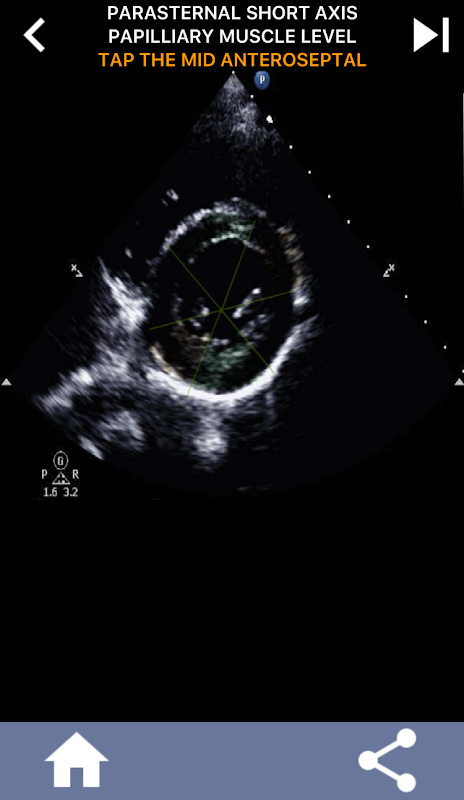

Memahami segmen jantung AHA (Persatuan Jantung Amerika) adalah amat penting bagi pakar sonografi jantung untuk berkomunikasi secara berkesan dengan pakar kardiologi yang menulis laporan. Dengan mengetahui kawasan anatomi tertentu dan segmennya yang sepadan, pakar sonograf boleh menerangkan dengan tepat dan menyampaikan sebarang kelainan atau penemuan, memastikan komunikasi yang jelas dan ringkas antara kedua-dua profesional.

Pemahaman ini menjadi sangat penting apabila pakar kardiologi berusaha untuk memastikan lokasi tepat masalah atau apabila doktor semasa panggilan mengenal pasti isu dalam kawasan tertentu, mendorong pakar sonograf untuk memaparkan segmen yang sepadan dengan tepat, seperti dinding pertengahan bawah. Oleh itu, memiliki pemahaman menyeluruh tentang segmen jantung AHA adalah set kemahiran yang penting.

Aplikasi ini akan menguji pengetahuan anda menggunakan imej gema sebenar, yang sering saya dapati sebagai kaedah pengajaran terbaik.